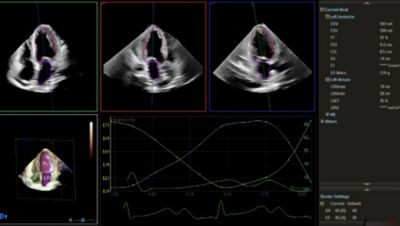

Automated full 3D quantification for volumes and functional assessment.

3DE image acquisition required less time than the multiple 2DE views for volume measurements. Analysis of the 3DE images was significantly faster than that of the 2DE images. Total time saved for acquisition and analysis combined was 82% in the fully automated mode and 63% even with manual editing.

[5] HeartModel study (4522 991 17141 * MAY 2016) by Dr. Roberto Lang: Automated transthoracic three-dimensional echocardiographic quantification of the left heart chambers